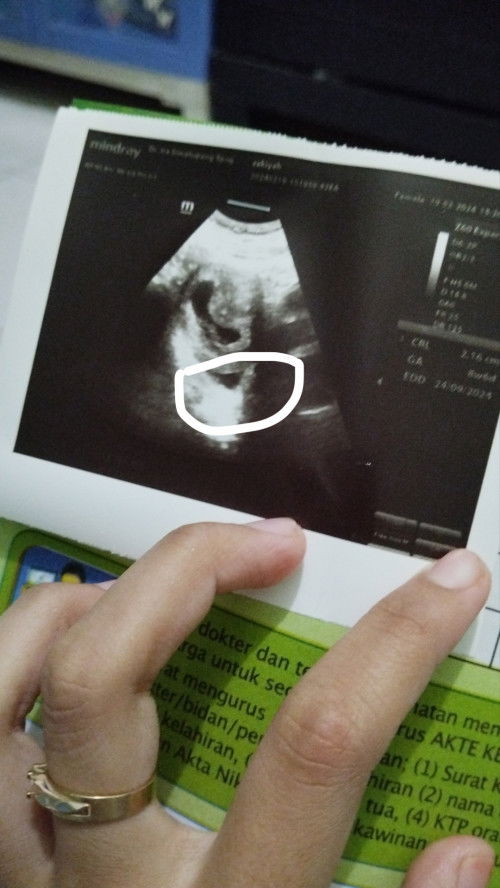

Mau nanya bun, foto yg aku lingkarin itu apa ya? Apa bnr kantung janin nya ada dua?

Usg 8weeks